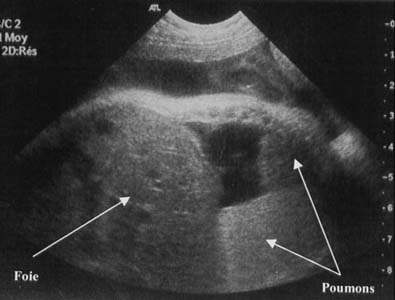

Kyste pleuro-péricardique